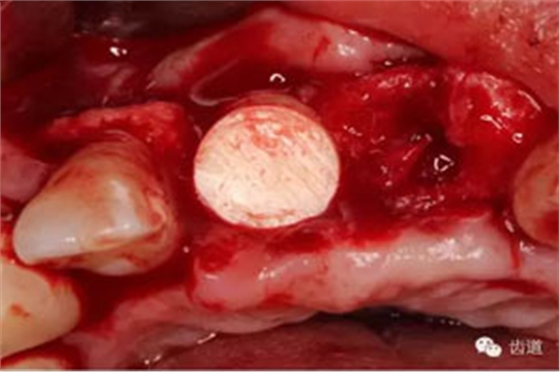

患者對(duì)美觀要求較高,與患者溝通后,擬定采用骨環(huán)技術(shù),同期種植并增加骨寬度和高度。

患者不愿才用自體骨移植,遂建議采用同種異體骨骨塊(皮質(zhì)骨)進(jìn)行骨環(huán)手術(shù)。 種植手術(shù):

骨環(huán)技術(shù)可以解決水平和垂直向的骨不足,但一般采用自體骨。自體骨雖然是骨移植的金標(biāo)準(zhǔn),但是需要在第二術(shù)區(qū)取骨,患者疼苦較大。同種異體骨塊來(lái)自于人類,和自體骨的結(jié)構(gòu)非常類似,成骨性能良好。故筆者選用同種異體骨塊進(jìn)行骨環(huán)手術(shù),在國(guó)內(nèi)外都是首次。該病例筆者隨訪觀察了一年,目前骨環(huán)比較穩(wěn)定。 白石 男 重慶醫(yī)科大學(xué)附屬口腔醫(yī)院種植科主治醫(yī)師,講師,碩士; 國(guó)際種植協(xié)會(huì)高級(jí)??漆t(yī)師,華西口腔醫(yī)學(xué)院碩士畢業(yè)生; 從事種植外科和種植修復(fù)臨床工作10年; 曾接受系統(tǒng)化種植培訓(xùn),有豐富口腔種植治療經(jīng)驗(yàn),擅長(zhǎng)復(fù)雜種植的設(shè)計(jì)與修復(fù),對(duì)全口種植義齒、種植美學(xué)修復(fù)技術(shù)和常規(guī)精密義齒修復(fù)有較深研究。 參加國(guó)內(nèi)外多次會(huì)議,并屢次獲得病例比賽獎(jiǎng)勵(lì)。